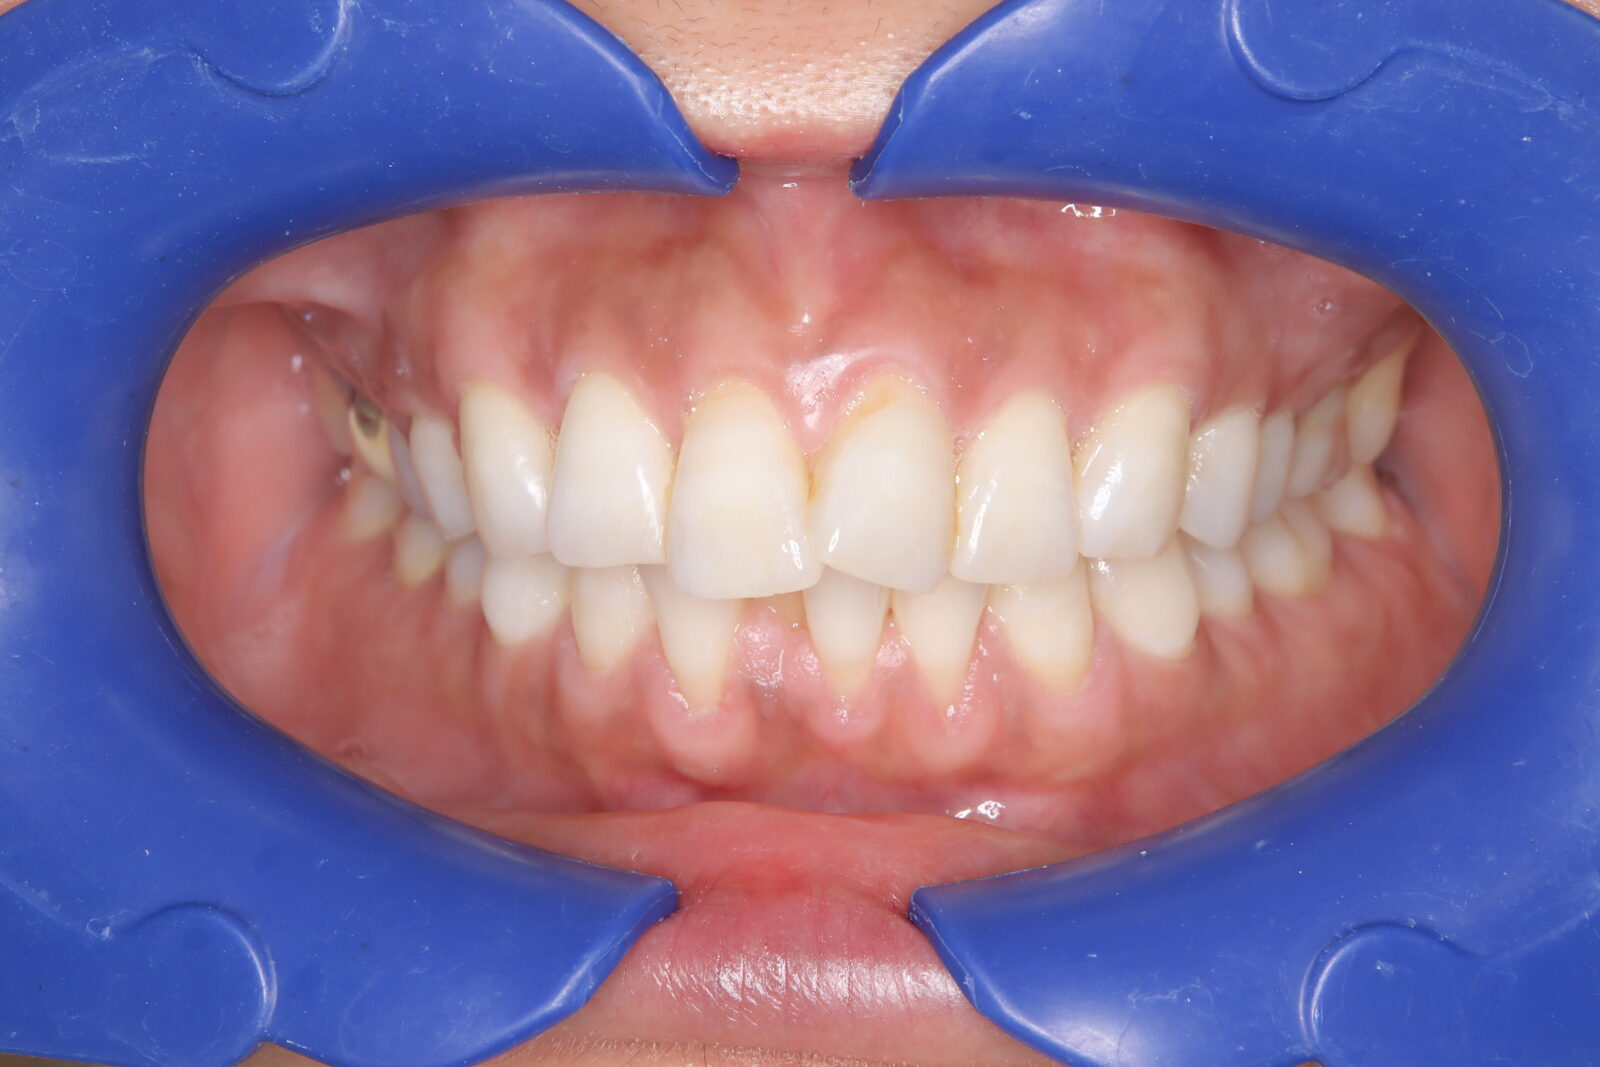

インビザライン(全体矯正)+ホワイトニングコースの症例

上下の前歯の歪みと奥歯のすれ違いをインビザライン(全体矯正)とホワイトニングで綺麗に矯正。

・費用:935,000円(税込)

・治療期間:30ヶ月

・通院回数:30回

・31歳女性

-リスクと副作用-

・長時間マウスピースを装着するため、むし歯や歯周病のリスクがある。治療後はリテーナーを装着しないと後戻りしてしまうリスクがある。

・ホワイトニング剤の影響で知覚過敏が起こる可能性がある。色が徐々に戻る可能性がる。